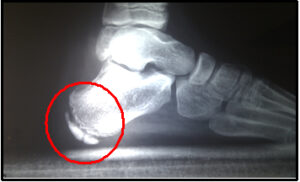

La Enfermedad de Sever o apófisis calcánea es una causa frecuente de dolor en el talón infantil. Suele aparecer entre los 7 y los 12 años de edad y es más frecuente en el género masculino y en aquellos niños que realizan actividad deportiva.

La apófisis calcánea es una inflamación aguda del cartílago por el desarrollo del talón. Durante el periodo de crecimiento se genera tensión muscular en el Tendón de Aquiles y la fascia del pie.